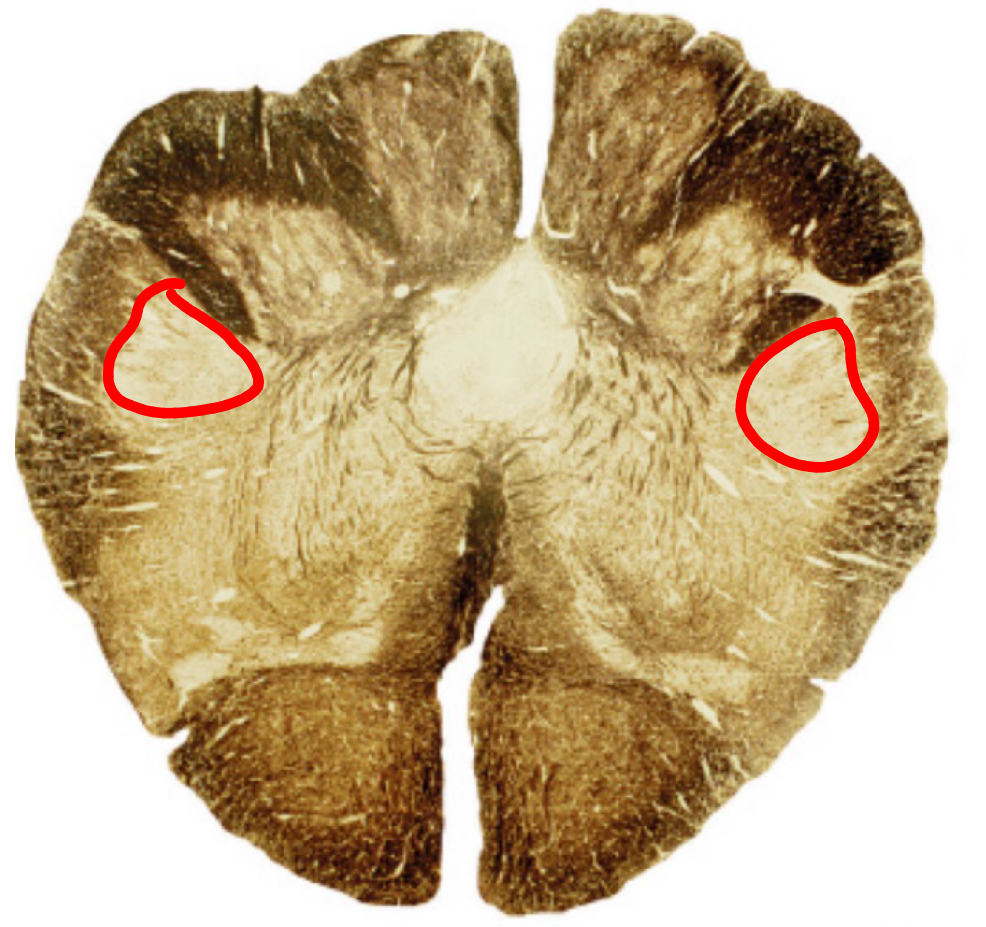

medial lemniscus rostral medulla

inferior cerebellar peduncle rostral medulla

inferior olivary complex rostral medulla

reticular formation rostral medulla

pyramidal tracts rostral medulla